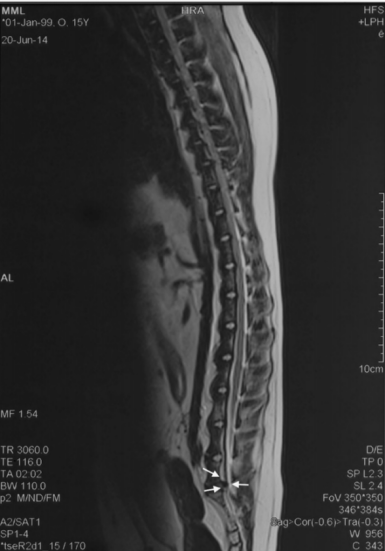

这只雌性混种犬就诊时情况令人揪心:后肢软弱无力,走路时膝盖弯曲变形,连最基本的爬楼梯都成了奢望,还出现了尿失禁症状。检查显示,它除了患有DLSS外,还伴有双膝骨关节炎。触诊时,腰骶部的疼痛反应明显,膀胱肿大,尾部张力减弱,种种迹象都表明病情已相当严重。

3. 精准注射将3000多万个细胞注入腰椎病变部位,同时在其膝关节内注入1500多万个细胞